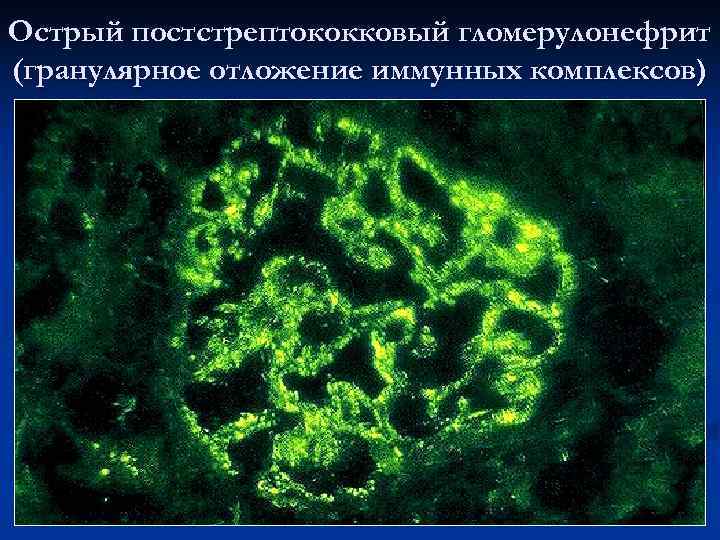

Механизм остро го диффузного гломерулонефрита